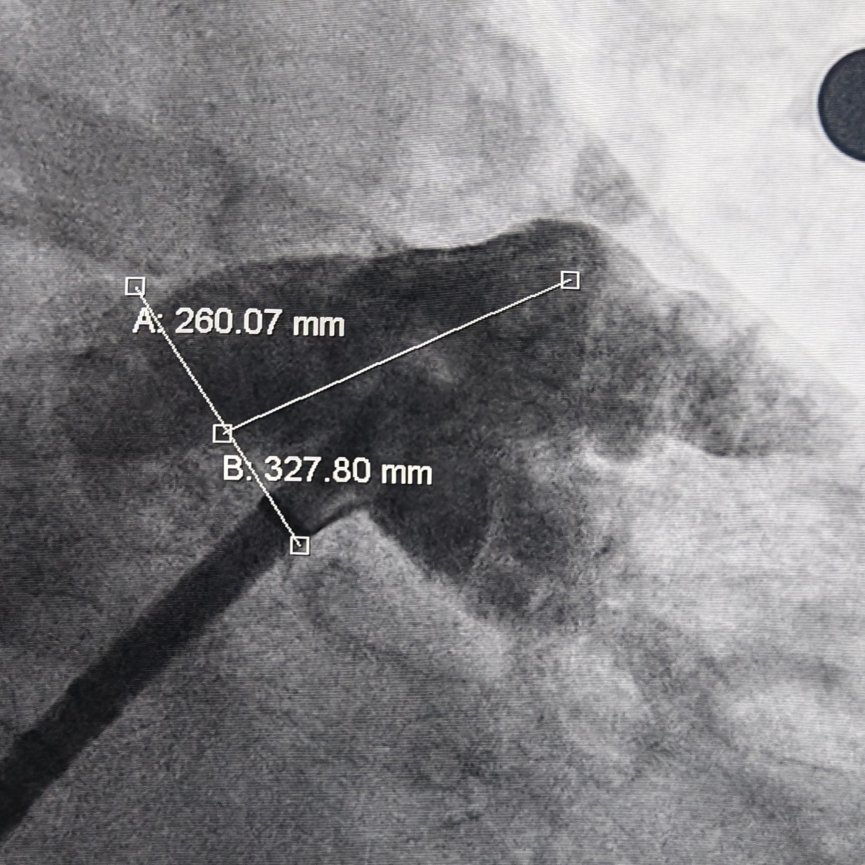

肝位左心耳测量,开口26mm,上叶深度32mm

封堵策略:术前CT评估为仙人掌型心耳,鞘管走上叶深度在32mm左右,展开时减少露肩,增加封堵器稳定性。

器械选择:本例术中肝位左心耳测量,开口26mm,深度空间足够,综合考虑选择MemoLefort 32型封堵器,保证封堵器稳定释放。

本例患者卒中风险极高(CHA₂DS₂-VASc 6分),且出血风险高(HAS-BLED 5分),LAAC可同时解决卒中预防和抗凝矛盾。随着患者年龄增大,合并其他疾病的增加,卒中风险急剧增加,一次封堵终身获益。本例术前造影发现心耳整体呈仙人掌型,开口直径26mm,主叶较深,深度32mm,考虑到仙人掌型心耳远端分叶会牺牲一些有效空间,封堵器选择需结合其稳定性和解剖结构的适配性,为保证压缩比,选择使用32型封堵器,避免封堵器突出至左心房。